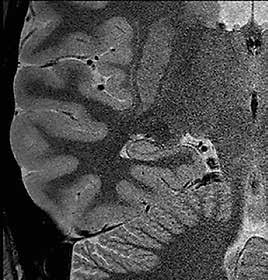

Ziel der Forschungen an der Universität Bordeaux war die hochaufgelöste und detailreiche Darstellung spezieller Hirnareale, wie des Hippocampus oder des Claustrum. Diese Regionen hatte Prof. Tourdias schon am 7T-System bei seinem Aufenthalt an der Stanford-Universität studiert. Nun war es mit der AiCE-Technologie möglich, vergleichbar aufgelöste Bilder auch bei 3T in akzeptabler Untersuchungszeit zu erzeugen (siehe Abb. 5 a und b).

Abb. 5 a + b: Hochaufgelöstes Bild des Hippocampus; 0,15 mm x 0,15 mm; 2 mm Schichtdicke; rechts mit AiCE-Rekonstruktion. Mit freundlicher Genehmigung des Unversitätsklinikums Bordeaux. Abb. 6 a + b: Hochaufgelöstes Bild des Knies; 0,15 mm x 0,15 mm (interpoliert); 1 mm Schichtdicke; rechts mit AiCE-Rekonstruktion.